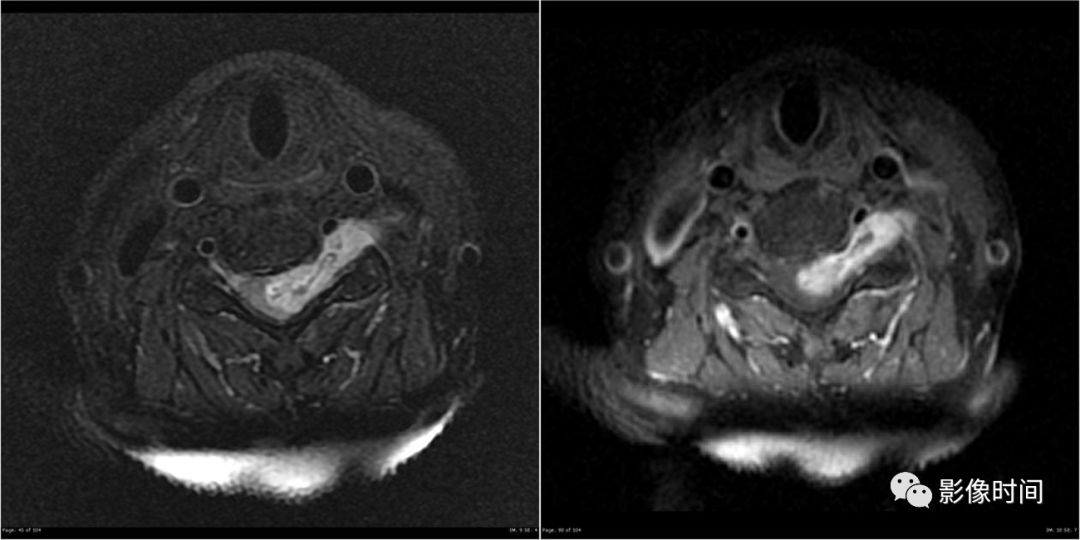

2裸面征

裸面征(naked facet sign),又称反汉堡面包征(reverse hamburger bun sign)

当脊椎小关节脱位时,上关节突脱位可位于上关节突后方,关节面向下显露,表现为关节面裸露,为裸面征(黄箭)。脱位可单侧或双侧出现;本例为左侧脱位,右侧为半脱位:可见上关节突(红箭)外移,相对下关节面显露,表现为关节面部分裸露(白箭之间)。

这是屈曲分离型损伤的特点,提示有严重的韧带损伤和脊柱不稳。

上图为 45 岁男性,交通事故后行轴位 CT 检查。显示右侧颈椎汉堡包征异常。双侧关节突不同程度分离、移位。

典型病例

正常汉堡包征的小关节(下图);外伤后,CT 骨窗示其前部「面包」(上关节突,黑箭)后移,位于下部「面包」(下关节突,白箭)的后方,关节面裸露。